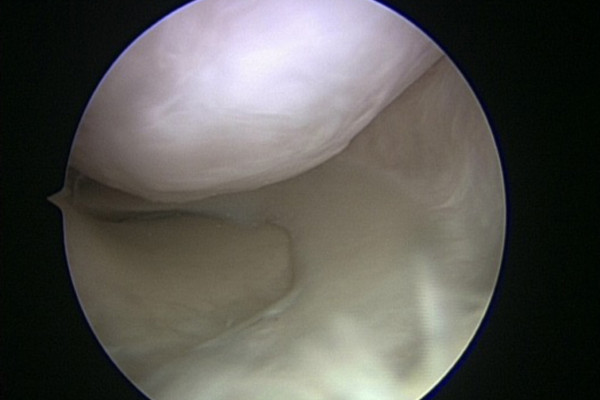

Refixation des Knorpelstückes

Situation nach Refixation des Knorpelstückes mittels resorbierbarer Nägel